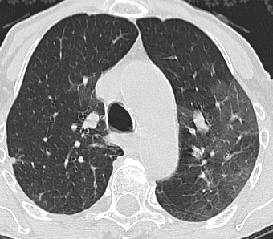

• Pulmonary infarct

• 10% embolic episodes result in infarction

• Infarction more common in those with underlying cardiopulmonary disease

• May develop immediately or delayed 2-3 days following embolus

• Any size or shape but classically cone shaped in periphery of lower lobes

• Often associated with small pleural effusion

• Evolution: initially ill-defined, over time become sharply defined

• 50% clear completely usually within 3 weeks

CT/HRCT

• Mosaic perfusion, usually less well defined than pattern with small airways disease

• Due to vascular obstruction with areas of hypoperfusion and overperfusion